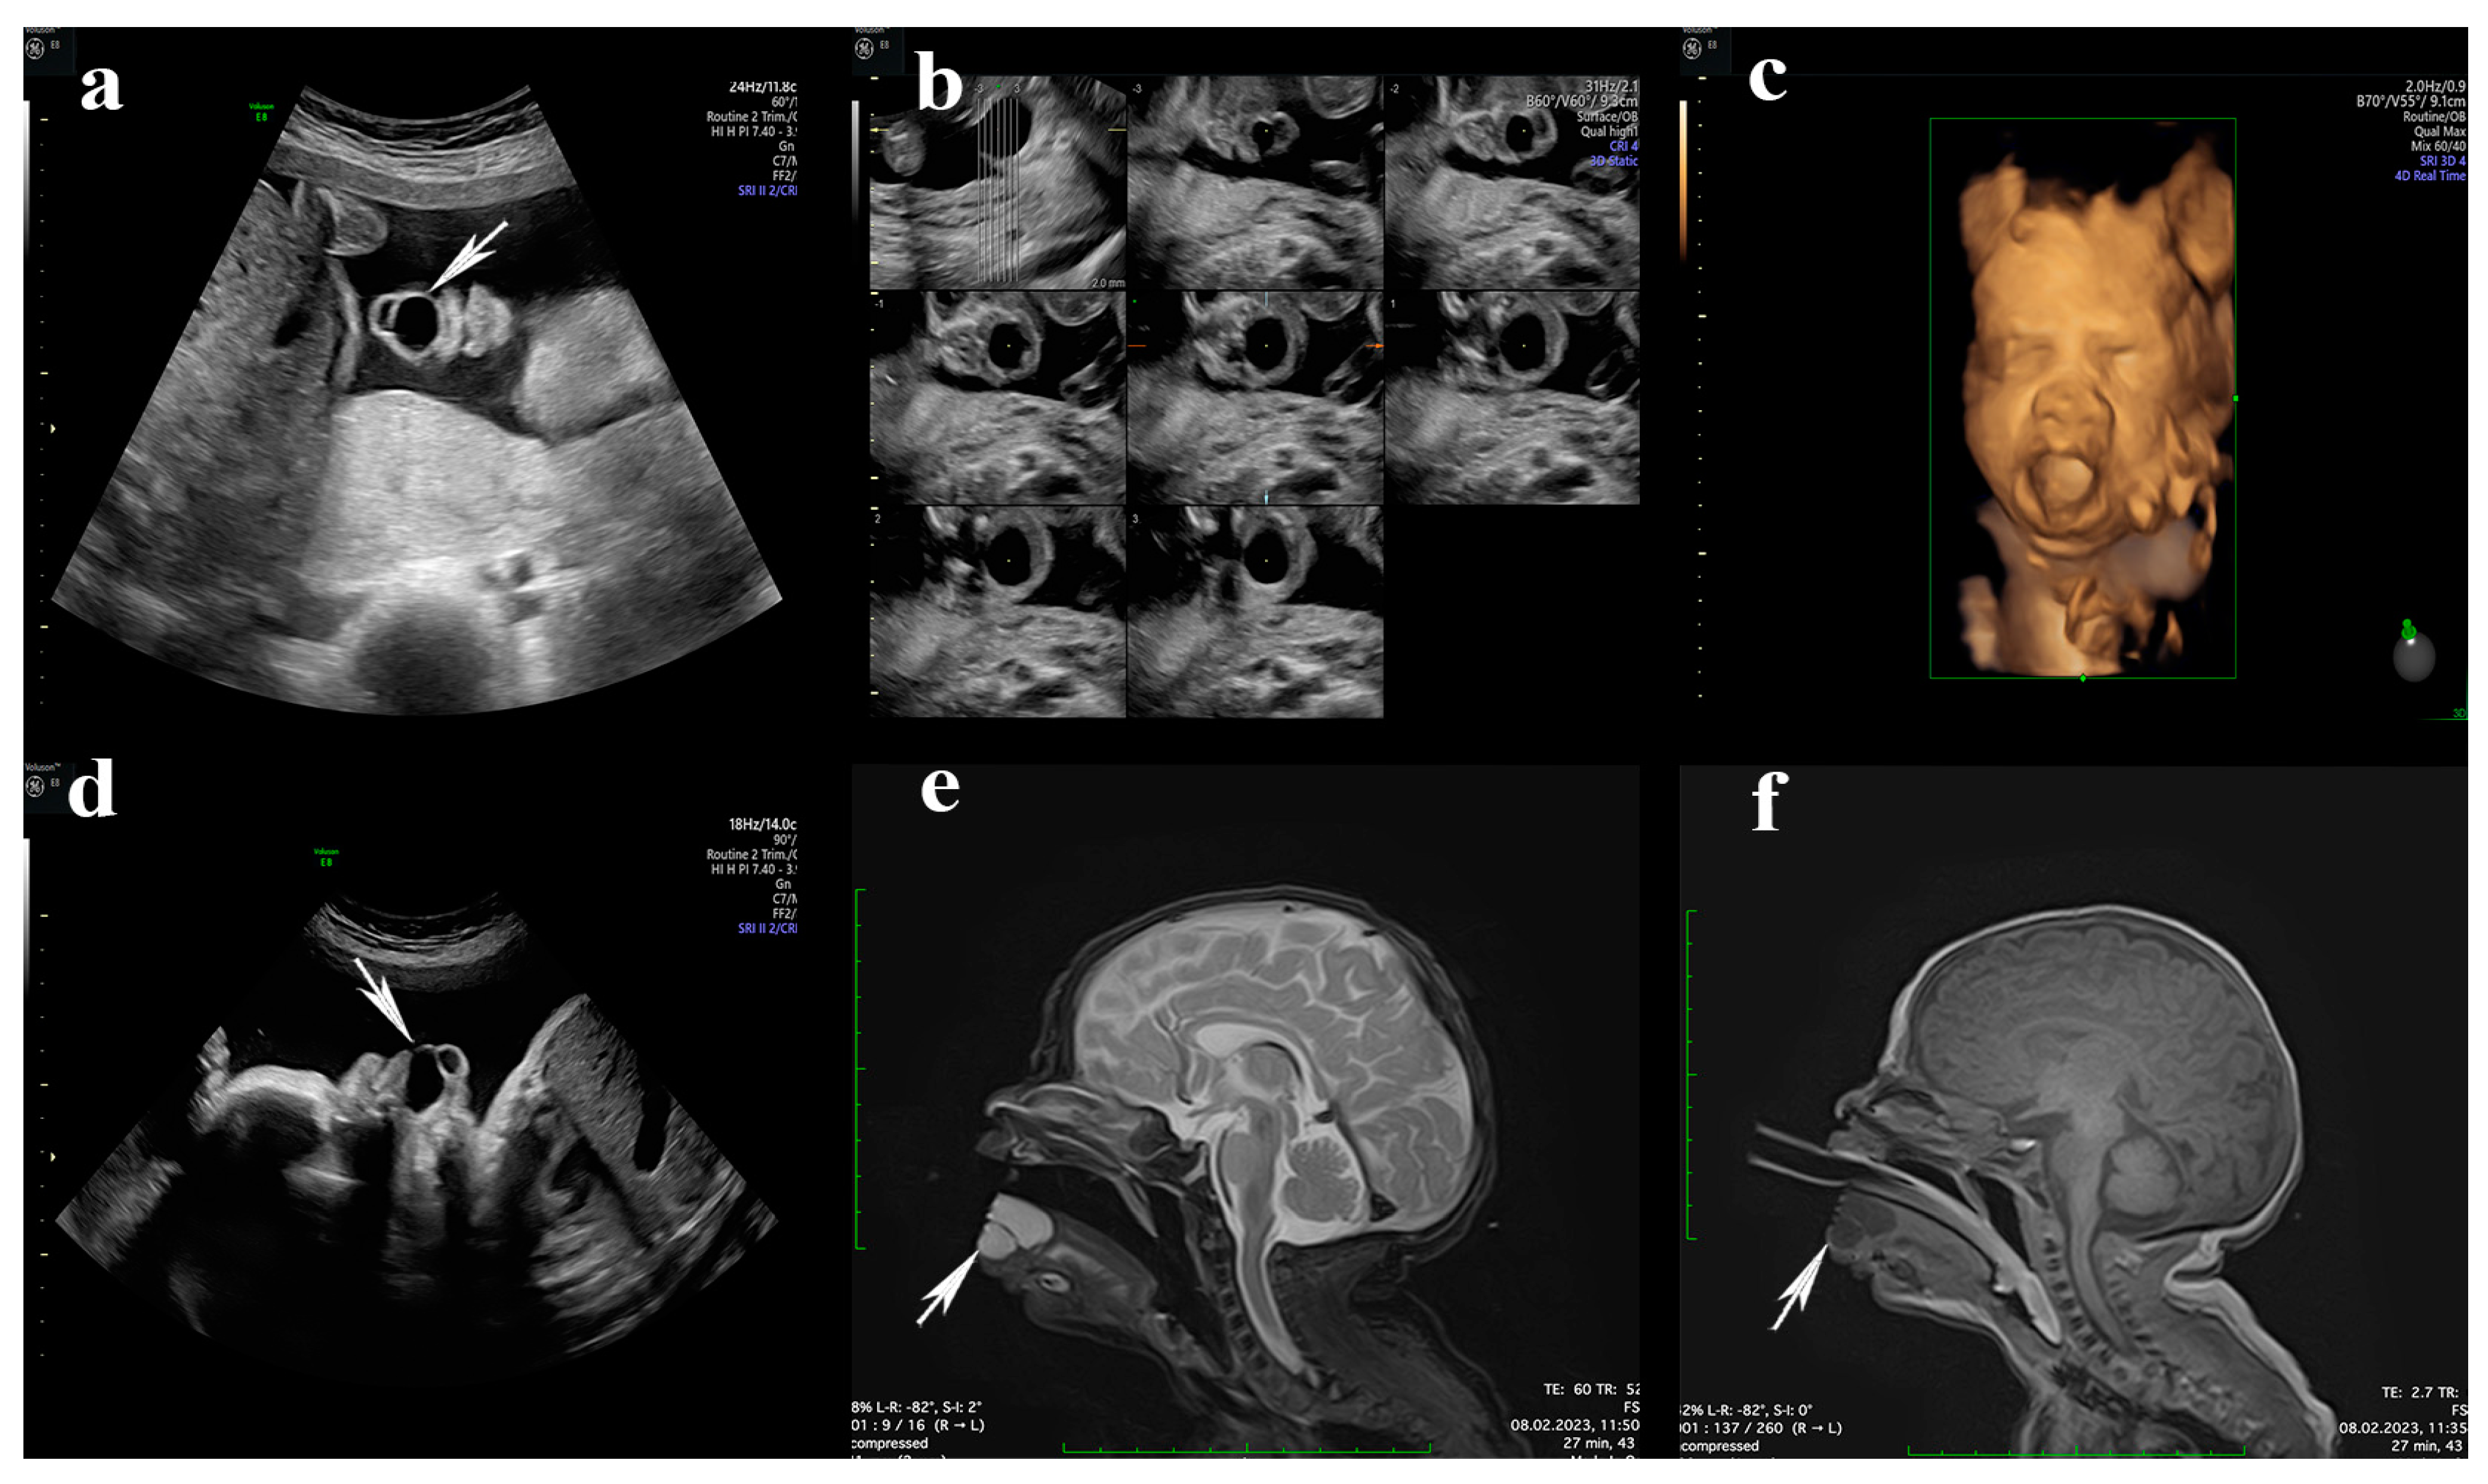

At 23 weeks of pregnancy, during the second-trimester screening, the presence of an orofacial cystic lesion with anterior lingual localization was discovered. The lesion was an anechoic, homogenous, septate cystic formation without solid areas, with well-defined edges and thin walls, measuring 2 × 0.8 × 0.5 cm. No Doppler signal was evident at this level. The cyst was mobile with tongue movements, and the tongue was slightly open, with the presence of swallowing movements (Figure 1a–c). No other ultrasound abnormalities or polyhydramnios were observed. The non-invasive fetal DNA test was performed and showed a normal karyotype.

In subsequent ultrasounds, no significant growth of this formation was observed, and the amniotic fluid was normal, which did not require the performance of an intrauterine intervention. The last ultrasound performed at 36 weeks highlighted the presence of swallowing movements (Videos S1 and S2) and the lack of an expansive process at the oropharyngeal level (Figure 1d).

Postnatally, on the eighth day of life, a preoperative MRI evaluation of the newborn was performed, which confirmed the absence of an extension at the level of the oropharynx (Figure 1e,f).

Figure 1. (a) The ultrasound image shows, at 23 weeks of gestation in the oral cavity, a bilocular cystic formation on the tongue (white arrow); (b) sections made using the TUI technique at the level of the tongue; (c) the 3D reconstruction of the lingual cyst formation; (d) sagittal incidence at 32 weeks to highlight the growth rate of the cyst (white arrow) and its relationship with the adjacent structures in the oropharynx; (e) postnatal, sagittal incidence of MRI showing an expansive cystic process, H-T2/H-T1, located on the ventral side of the tongue at approximately 21.7 × 18.2 × 15.8 mm with a septum of 1 mm and clear delimitation (white arrow), without signs of locoregional invasion, and without diffusion restriction. (f) The same incidence as endotracheal cannula exposure (white arrow show lingual cyst).